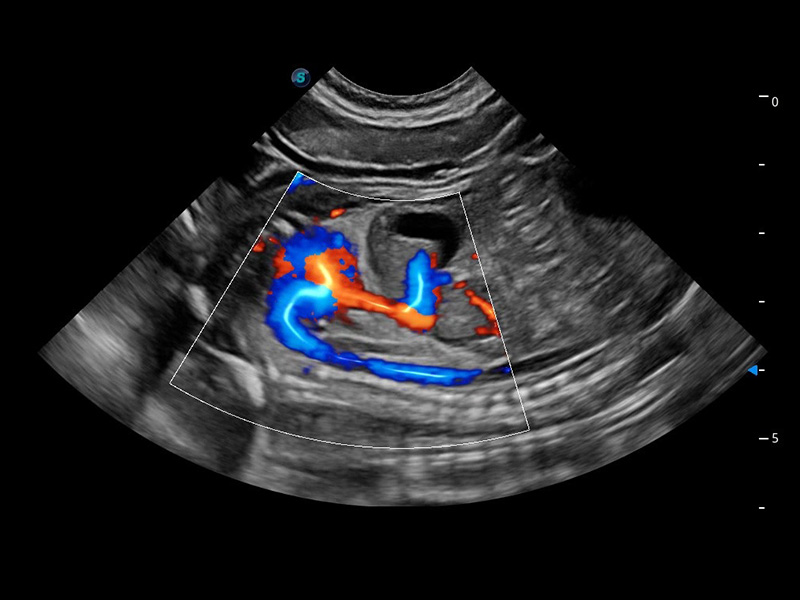

ProPet 60 作为一款高端台式动物超声设备,为动物医生的日常诊断提供了一系列贴合动物临床需求、解决临床实际问题的高级成像功能。凭借全系列高清探头,满足医生对腹部、心脏、生殖、浅表、肌骨等成像的所有需求,切实帮助您提升检查效率,提高诊断信心。

动物是人类最亲密的朋友和最值得信赖的伙伴。开立医疗也一直致力于探索动物专用的超声影像解决方案。 全新推出的ProPet系列,是开立在动物超声影像智能化、专业化、精准化的一次跨越式革新。动物不能用言语来表述自己的不适,通过超声影像,ProPet系列搭建了动物医生与不同物种沟通的“桥梁”,为动物医生注入了“治愈之力”。

兽用彩色多普勒超声诊断系统